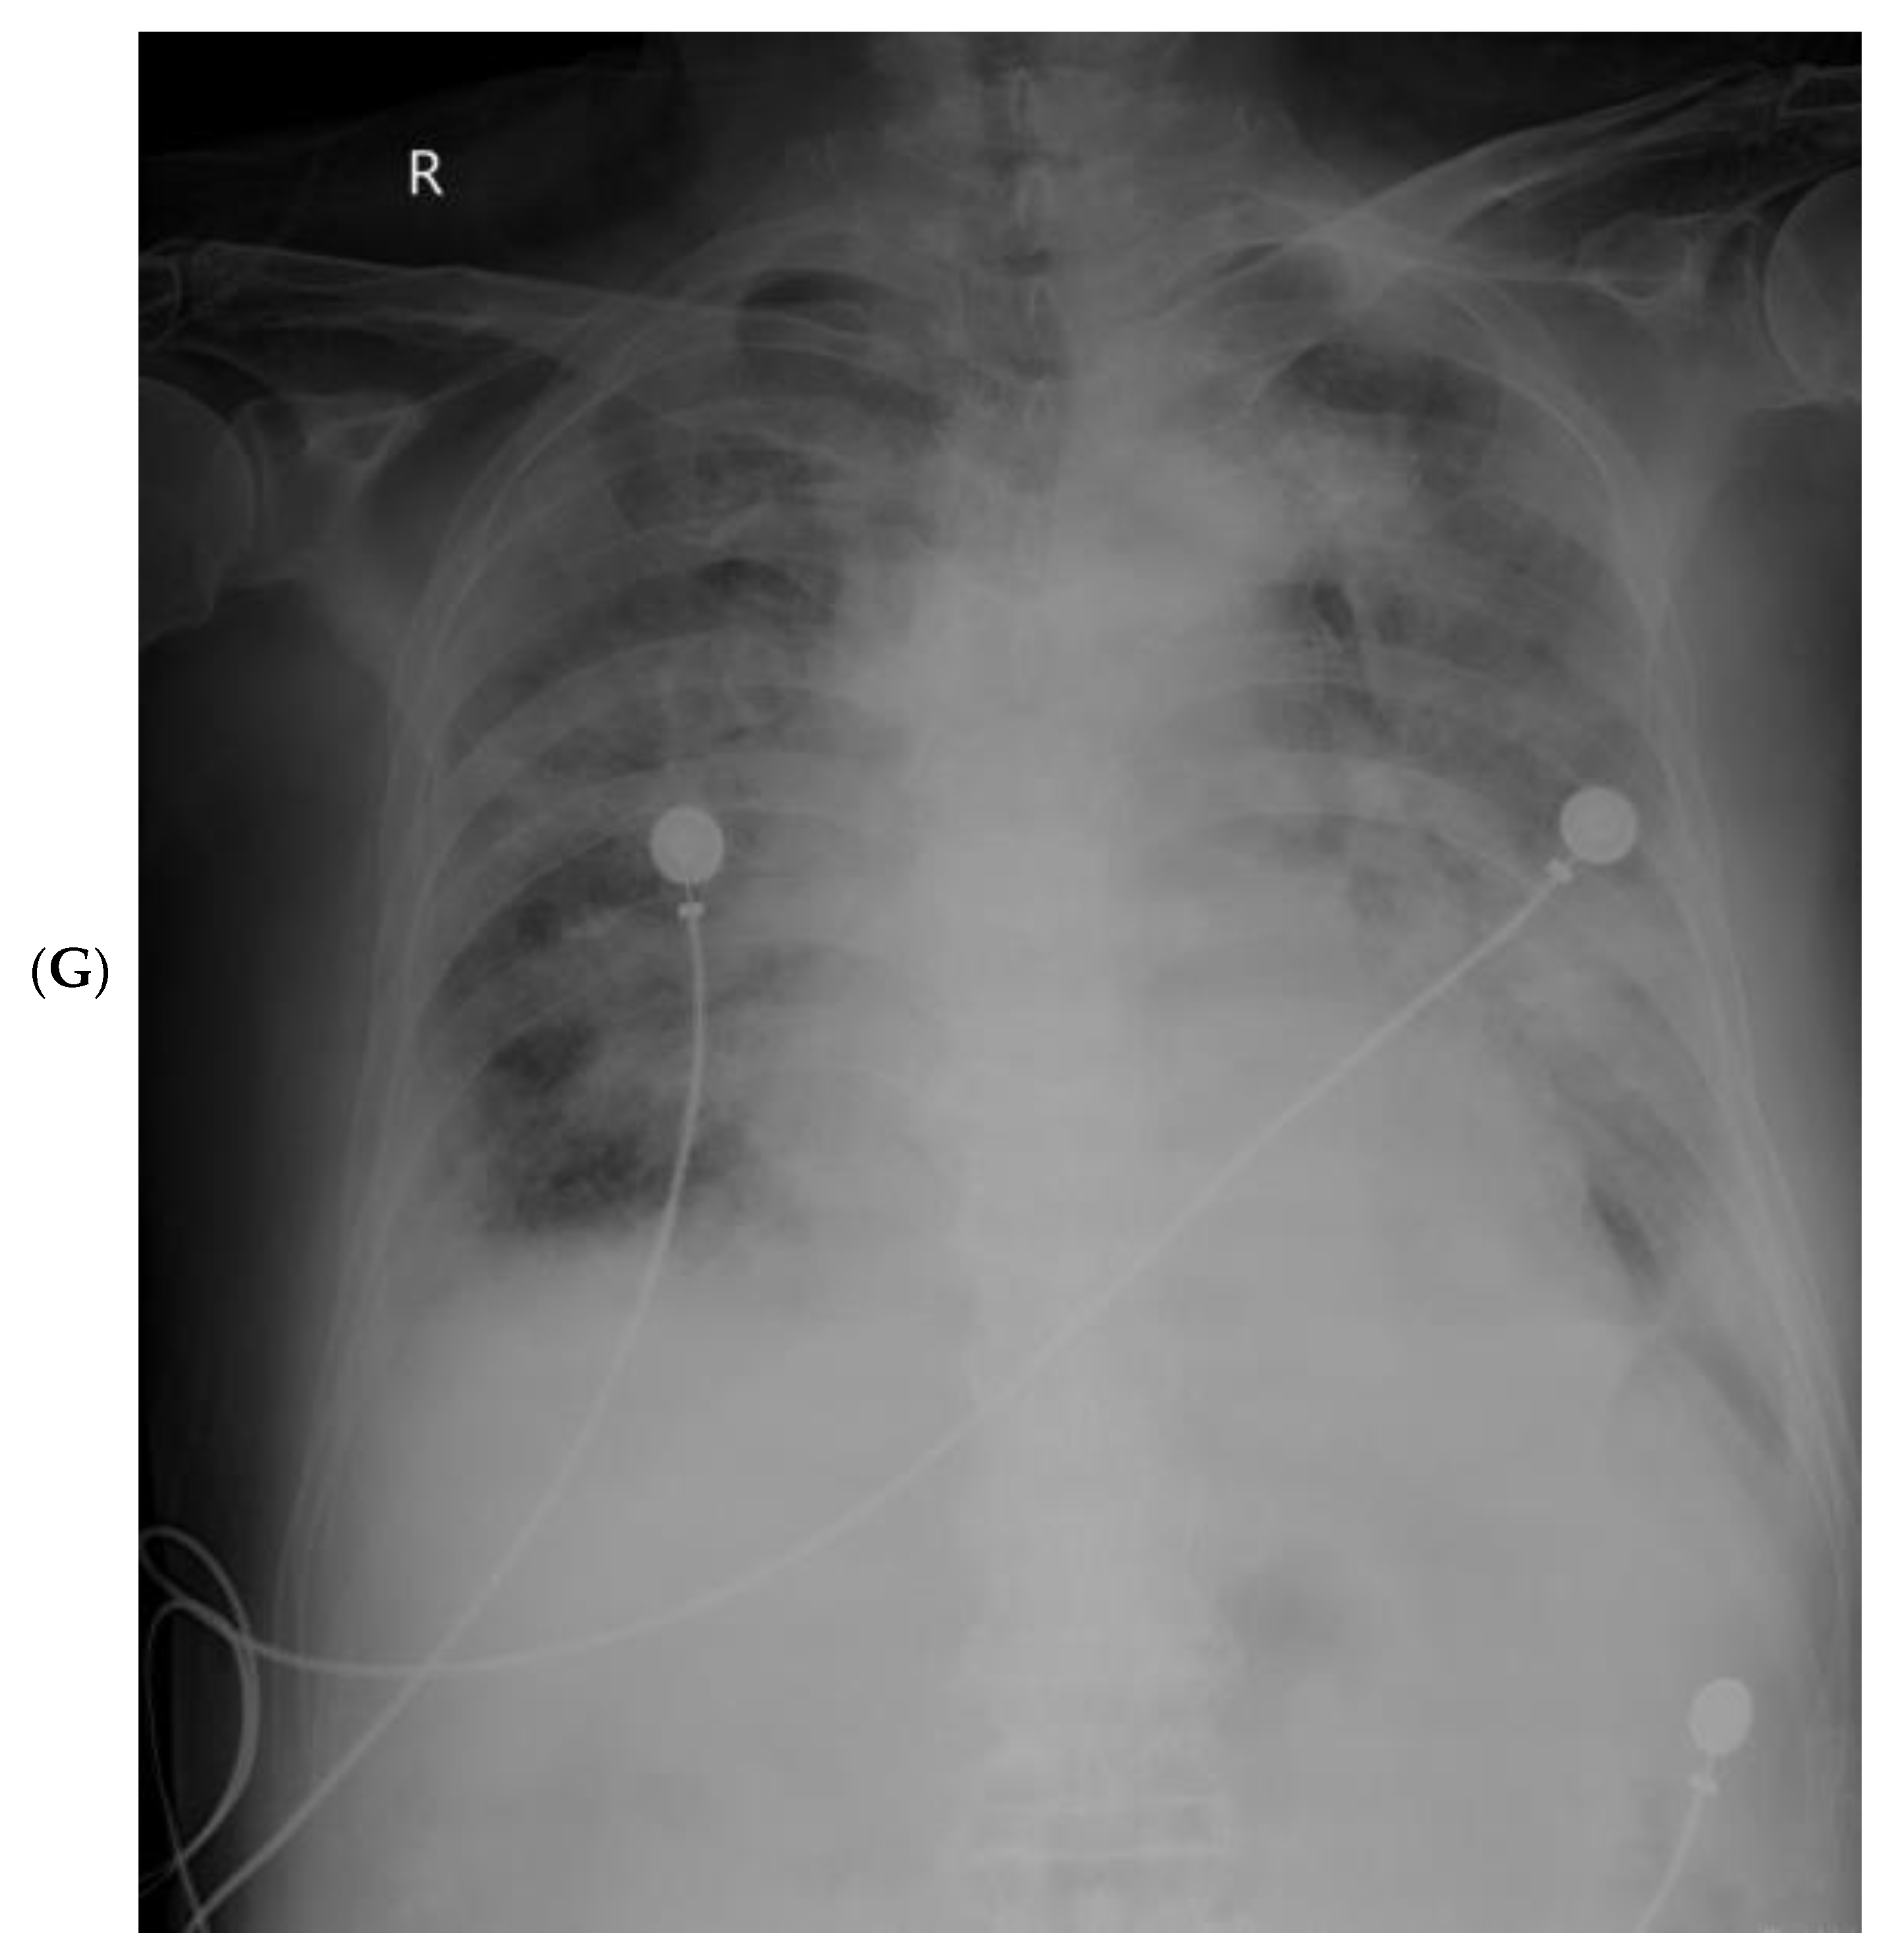

3.4. Imaging Changes in Disease Progression